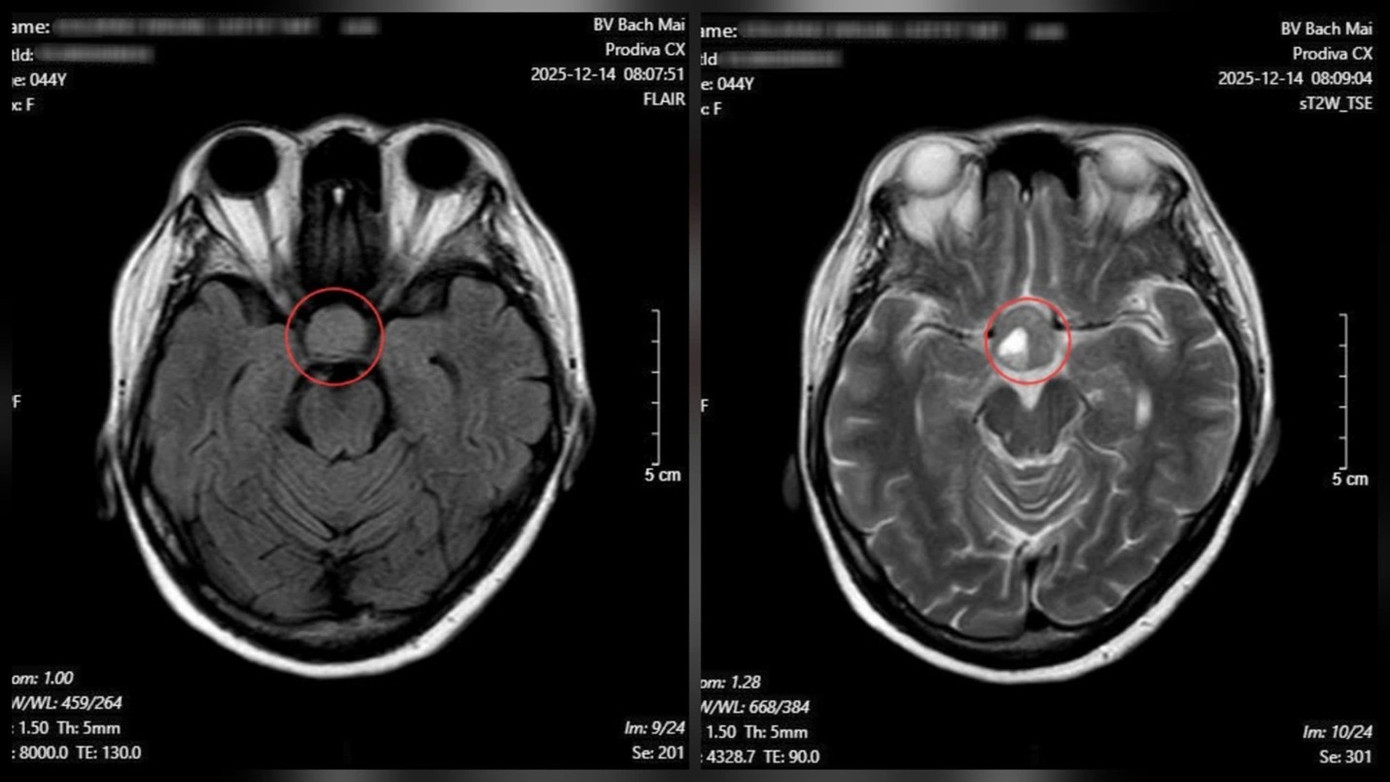

Từ các dấu hiệu nghi ngờ, bệnh nhân được chỉ định chụp cộng hưởng từ (MRI) sọ não. Kết quả cho thấy một khối u tuyến yên kích thước lớn (macroadenoma) với đường kính khoảng 26 × 21 mm, đang chèn ép cấu trúc thần kinh thị giác.

Kết quả chụp cộng hưởng từ (MRI) sọ não cho thấy một khối u tuyến yên kích thước lớn